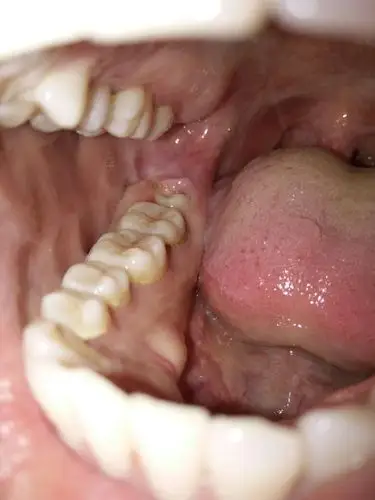

上下门牙牙龈红肿,出血半年多,求怎么治疗(有实拍图片) - 口腔医学

牙龈肿疼,今天早上起来发现肿的蛮大了.

牙龈肿了个肉坨怎么办多久会好(牙龈发炎肿痛怎么办) 服务器教程 第1

最后一颗牙齿上的牙龈红肿又痛,前两天吃了药好些了(吃了人工牛黄

这两天牙龈疼 疼的部分就是照片上的位置 最里面的位置 要怎么才能